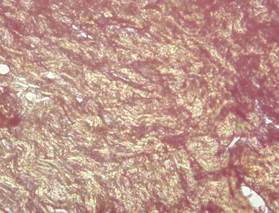

En la coloración se evidenció abundante proliferación dérmica de colágeno; con áreas de birrefringencia rojiza y verde amarillenta, indicando presencia de colágeno maduro tipo I y tipo III; lo que podría indicar la buena respuesta regenerativa del organismo frente al proceso de progresión de células infectadas con el agente etiológico, siendo estas técnicas utilizadas por Cardona et al. (2013a; 2013b) como indicador del grado de respuesta de reparación de tejidos en estados agresivos cutáneos.

Figura 3. Marcadas

áreas de birrefringencia rojiza, lo que indica presencia de colágeno maduro

tipo I (color rojo brillante) y moderada presencia de colágeno tipo III (color

verde-amarillento). Coloración EVG 40X.

Elaboración: Los autores.

La birrefringencia verde-amarillenta de las fibras observadas en la Figura 3, indica presencia de colágeno maduro tipo I. Existe policromía y al corte histológico no es homogéneo.